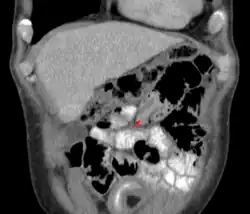

Uma intussuscepção é uma condição médica na qual uma parte do intestino se invagina (se dobra) por sobre outra seção do intestino, semelhante à maneira como as partes de um telescópio se retrai sobre a outra parte.[1] Muitas vezes pode resultar em obstrução. Poucas intussuscepções reduzem espontaneamente, mas, se não tratadas, a maioria levará a infarto intestinal, perfuração, peritonite e óbito.[2]

Um raio-x de abdômen pode ser indicado para verificar obstrução intestinal ou gás intraperitoneal livre. A última constatação implica que a perfuração intestinal já ocorreu. Algumas instituições utilizam enema de ar para o diagnóstico, e o mesmo procedimento pode ser utilizado para tratamento.[5]